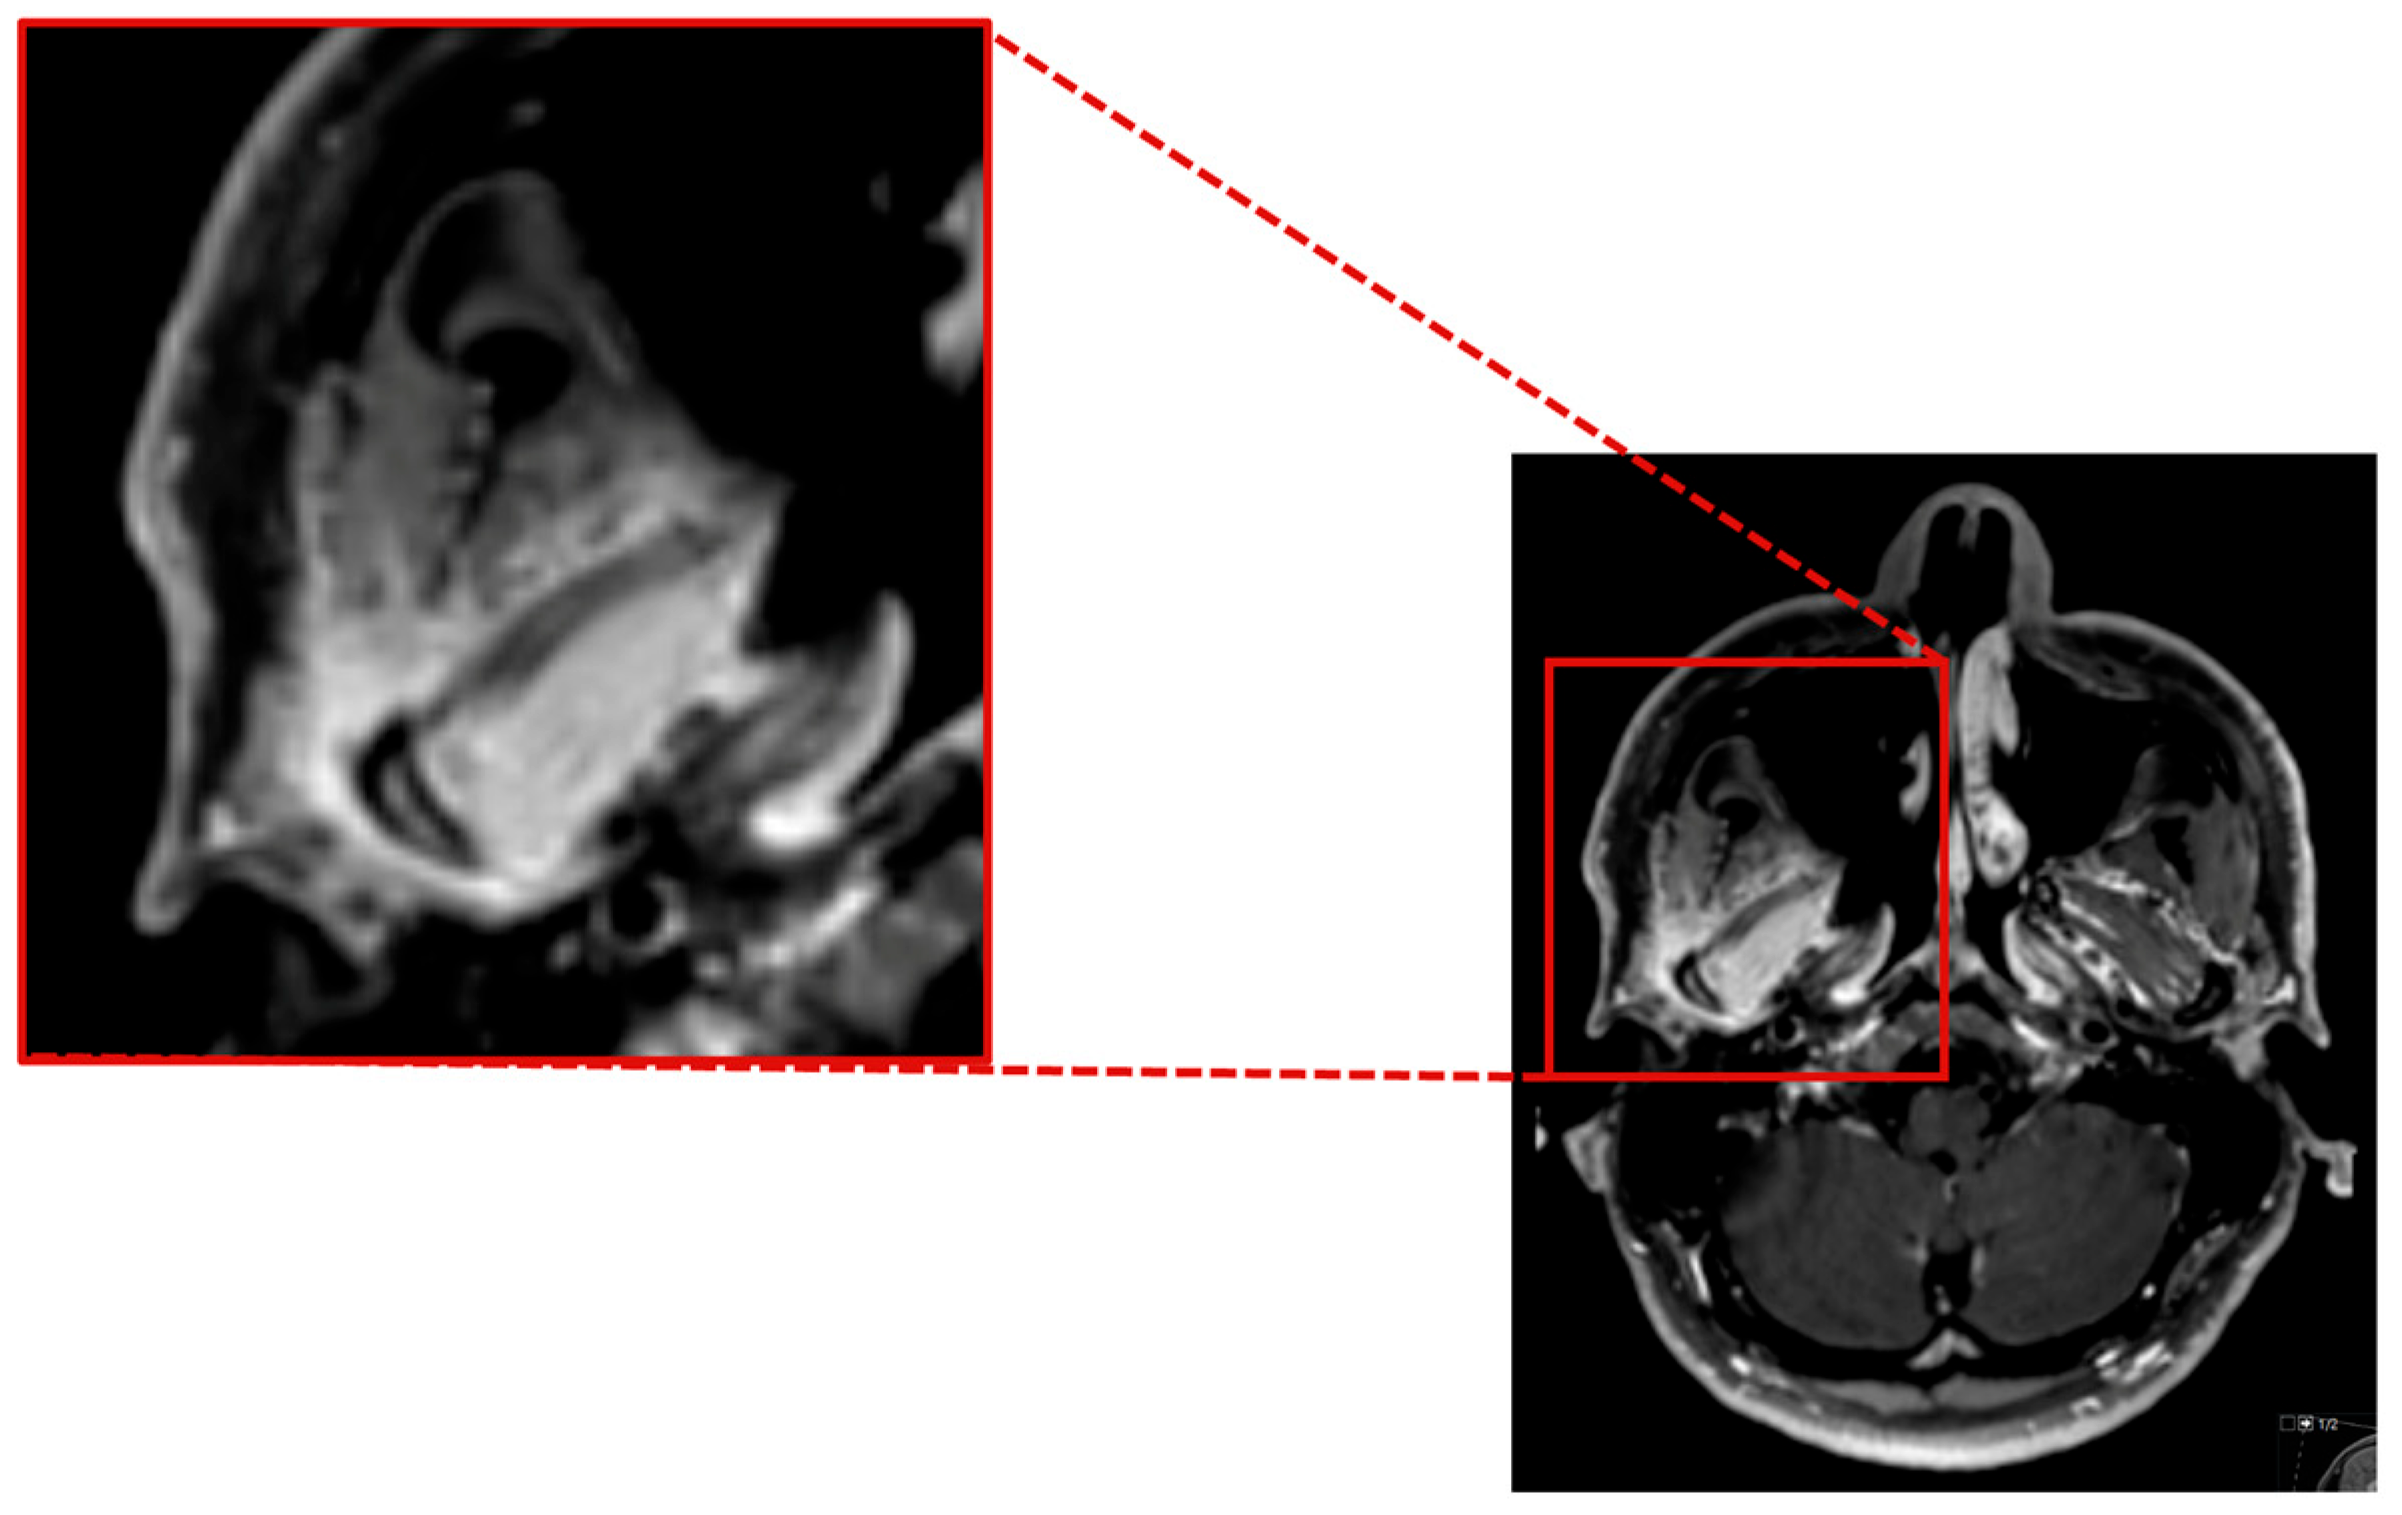

As the herpes simplex virus and Listeria tests PCR yielded negative results, the administration of aciclovir and ampicillin was discontinued. A follow-up MRI revealed inflammatory changes in the region of the right jaw joint and the masticatory muscles (Figure 3).

Figure 3.

Contrast enhanced axial T1 SPACE showing a marked inflammatory contrast enhancement of the mandible head and the surrounding soft tissue, especially the lateral pterygoidal and masseter muscle.